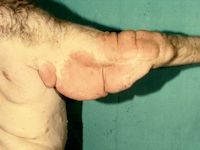

Plexiforme neurofibromen

Tumoren uitgaande van perifere zenuwen, spoelvormige cellen, lokaal invasief. Komt voor bij circa 10%, ontstaat vaak pas rond 4-5e levensjaar. Kunnen ontaarden in een maligne sarcoom (2-5%). Er is een diffuse vorm (grote subcutane zwellingen, slecht afgrensbaar van de omgeving, moeilijk te verwijderen) en een nodulaire vorm.

Plexiforme neurofibromen Plexiforme neurofibromen Plexiforme neurofibromen